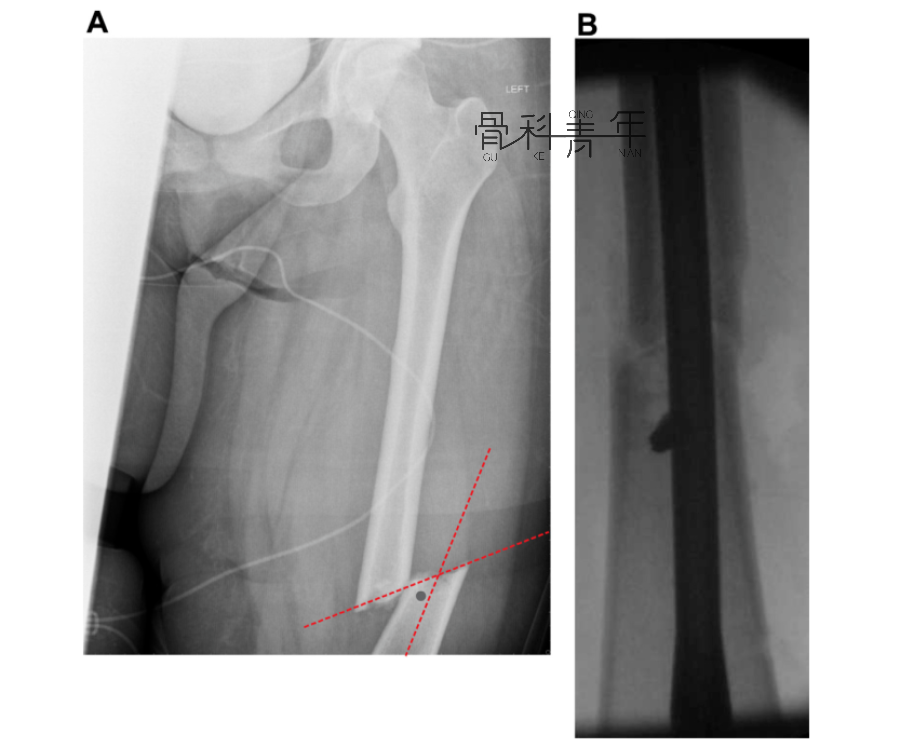

为了矫正股骨力线,在干骺端横行截骨(a横行虚线)后,截骨远端移位,此时髓内钉置入后应为偏心方可维持矫形,为了获得髓内钉位置,需要置入阻挡钉(b)。

图a所示该患肢与健侧相比,存在6.2°外翻和28mm短缩。图b红色轮廓为纠正力线后截骨近端的形态,绿色为同时纠正外翻和短缩后股骨近端的位置,依照绿色轮廓置入髓内钉,此时髓内钉进入截骨远端为偏心,为了维持髓内钉位置,阻挡钉置入位置明确。图d可见髓内钉及阻挡钉置入后情况。